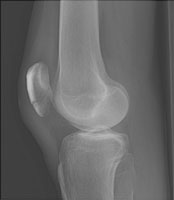

- Click on the image for a larger versionBLateral radiograph of the knee. This depicts the fracture through the inferior pole of the patella.